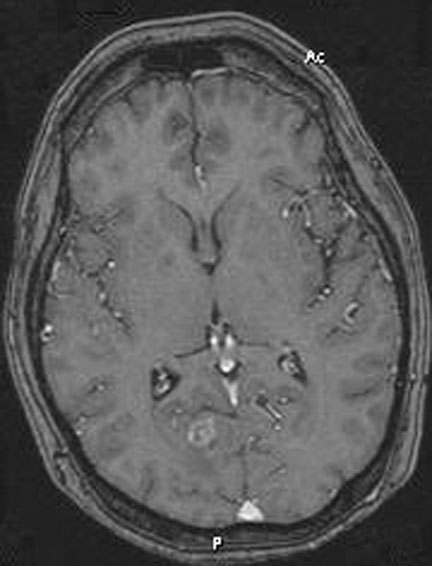

RNM de control a 3 meses. Observe la marcada reducción tumoral y desaparición del edema y del efecto de masa.

A las pocas semanas de la reintervención. Paciente logra caminar y ser independiente revirtió el déficit neurológico con sobrevida funcional de 8 meses de excelente calidad de vida.